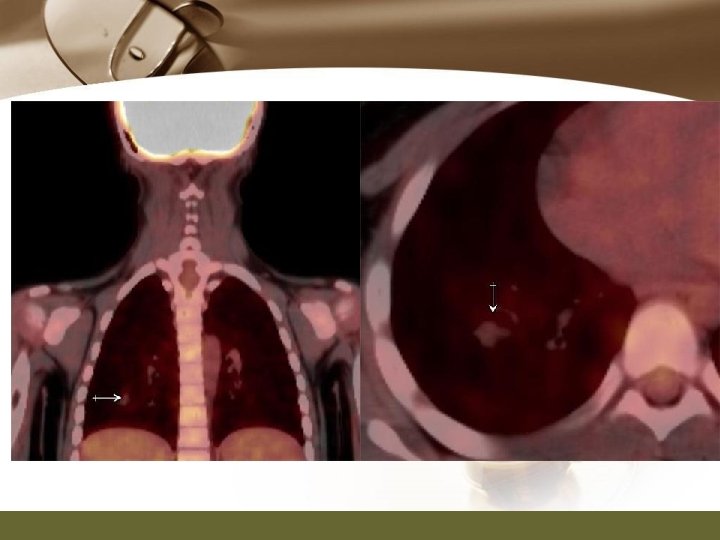

PET/CT and MRI

PET/CT Report v. PET/CT (03/07/52) v. A 2. 1 x 2. 2 cm hypermatabolic irregular rim enhancing mass with central hypodensity at left palatine tonsillar fossa, consistent with history of hamangioendothelioma. This is possible residual disease v. Mild focal bulging medical contour of right palatine tonsil without definite abnormal enhancing area, showing homogeneous FDG accumulation, small focal lesion cannot be excluded. Tissue diagnosis is recommended.

PET/CT Report v. Multiple hypermetabolic bilateral cervical lymph nodes (more on the left), likely nodal metastases. v. Multiple pulmonary nodules, probably pulmonary metastases. v. Multiple small hypermetabolic poorly osteolytic and nonosteolytic lesion, probably inhomogeneous marrow activity in child or foci of marrow infiltration. Correlation with other imaging modality such as bone scan is recommended